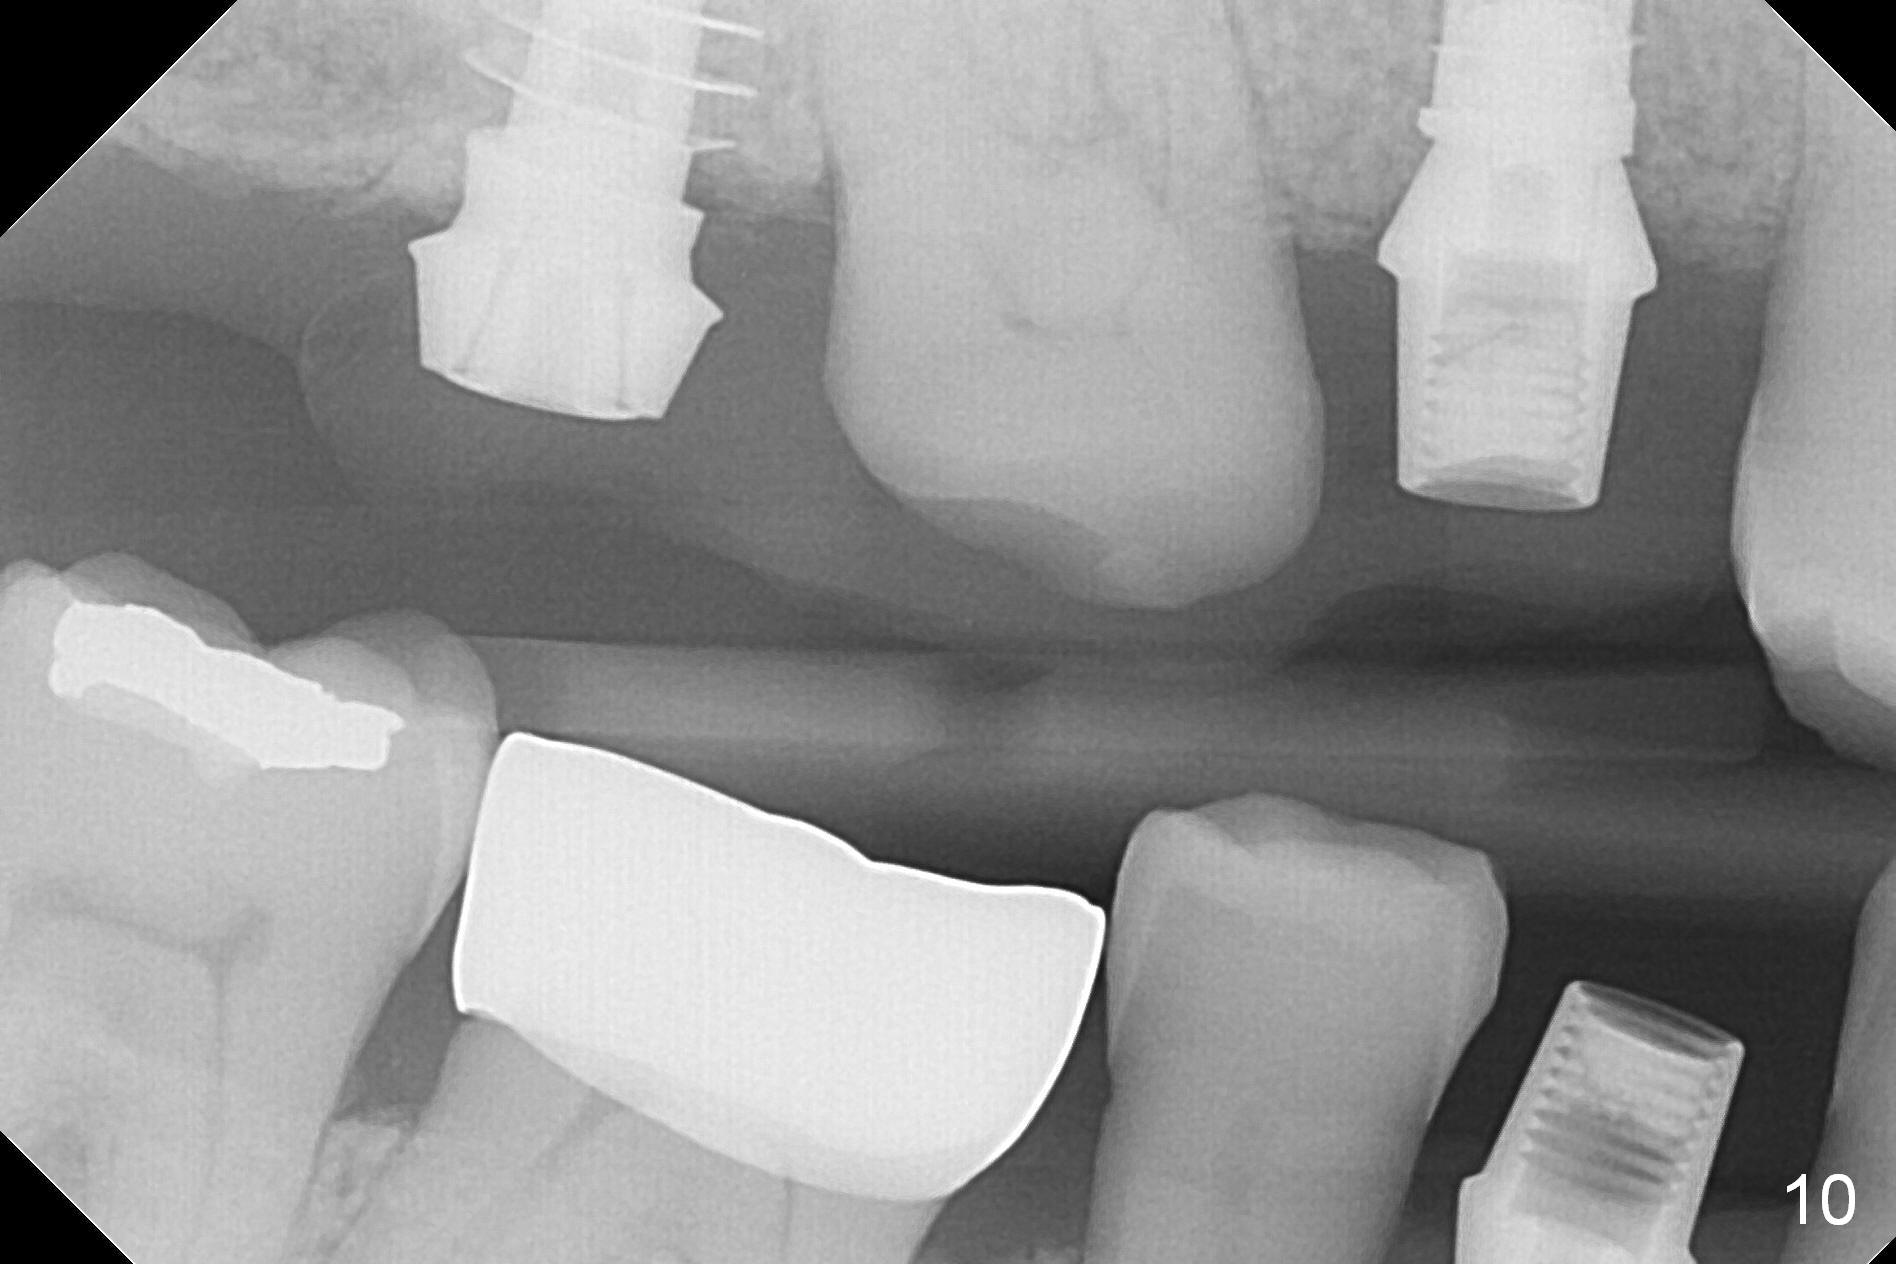

In fact the upper provisional has been extended to cover #2-4 three months postop. When the patient returns again, it is approximately 4 months postop for #2 and 4 (Fig.9,10) and 3 months for #28. Reline or make the provisional so that the teeth #5 and 29 will be intruded (Fig.11 preop pan for comparision). The tooth #30 appears to have been intruded for the past 4 months. The provisional at #3 is short so that the tooth #30 may be able to erupt (Fig.12).

The right posterior final restorations (Fig.14) are fabricated as planned: increase in vertical height (Fig.15). The increase is minimal (Fig.14, 17(#2 limited crown height), 16 (#2 crown being thin *)). Fig.17,18 are taken immediately post cementation. There is no bone loss 10 months post cementation (Fig.19,20). The gingiva is healthy around the implant crowns (#2, 4 and 28) 1 year 4 months post cementation (Fig.21,22).